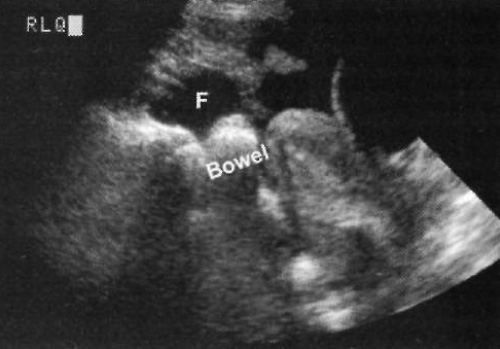

Фото 4. Жидкость в правом нижнем квадранте живота. Буквой «F» обозначена жидкость, которая оттесняет кишечник от боковых стенок живота в области нижнего квадранта